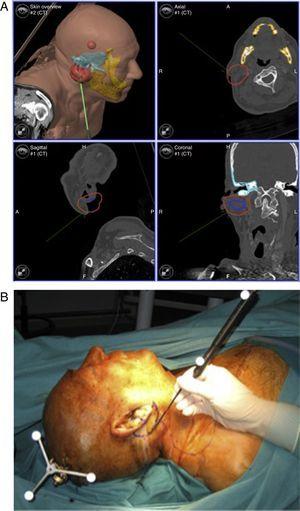

Biopsia guiada

Las biopsias fueron los primeros procedimientos donde se empleó la tecnología de la navegación en la cabeza y el cuello3,7. Es particularmente útil en espacios anatómicos de difícil acceso y en casos de tumores próximos a estructuras vitales3 (órbita, espacio pterigomaxilar e infratemporal, base del cráneo) (fig. 1). También se ha empleado recientemente en la biopsia del ganglio centinela en el manejo del cáncer de parótida12.

Diseño de trayectorias para acceso a un tumor del espacio pterigomaxilar.

Figura 1.

(0,19MB).